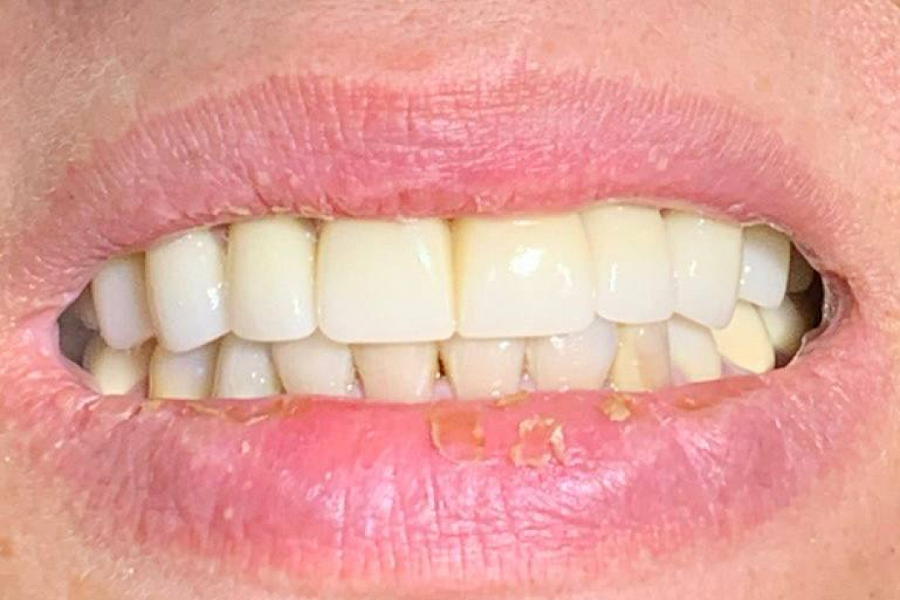

Получили очень хороший эстетический результат и стабилизацию состояния агрессивного пародонтита. Пациентку зубы больше не беспокоят.

Результат лечения